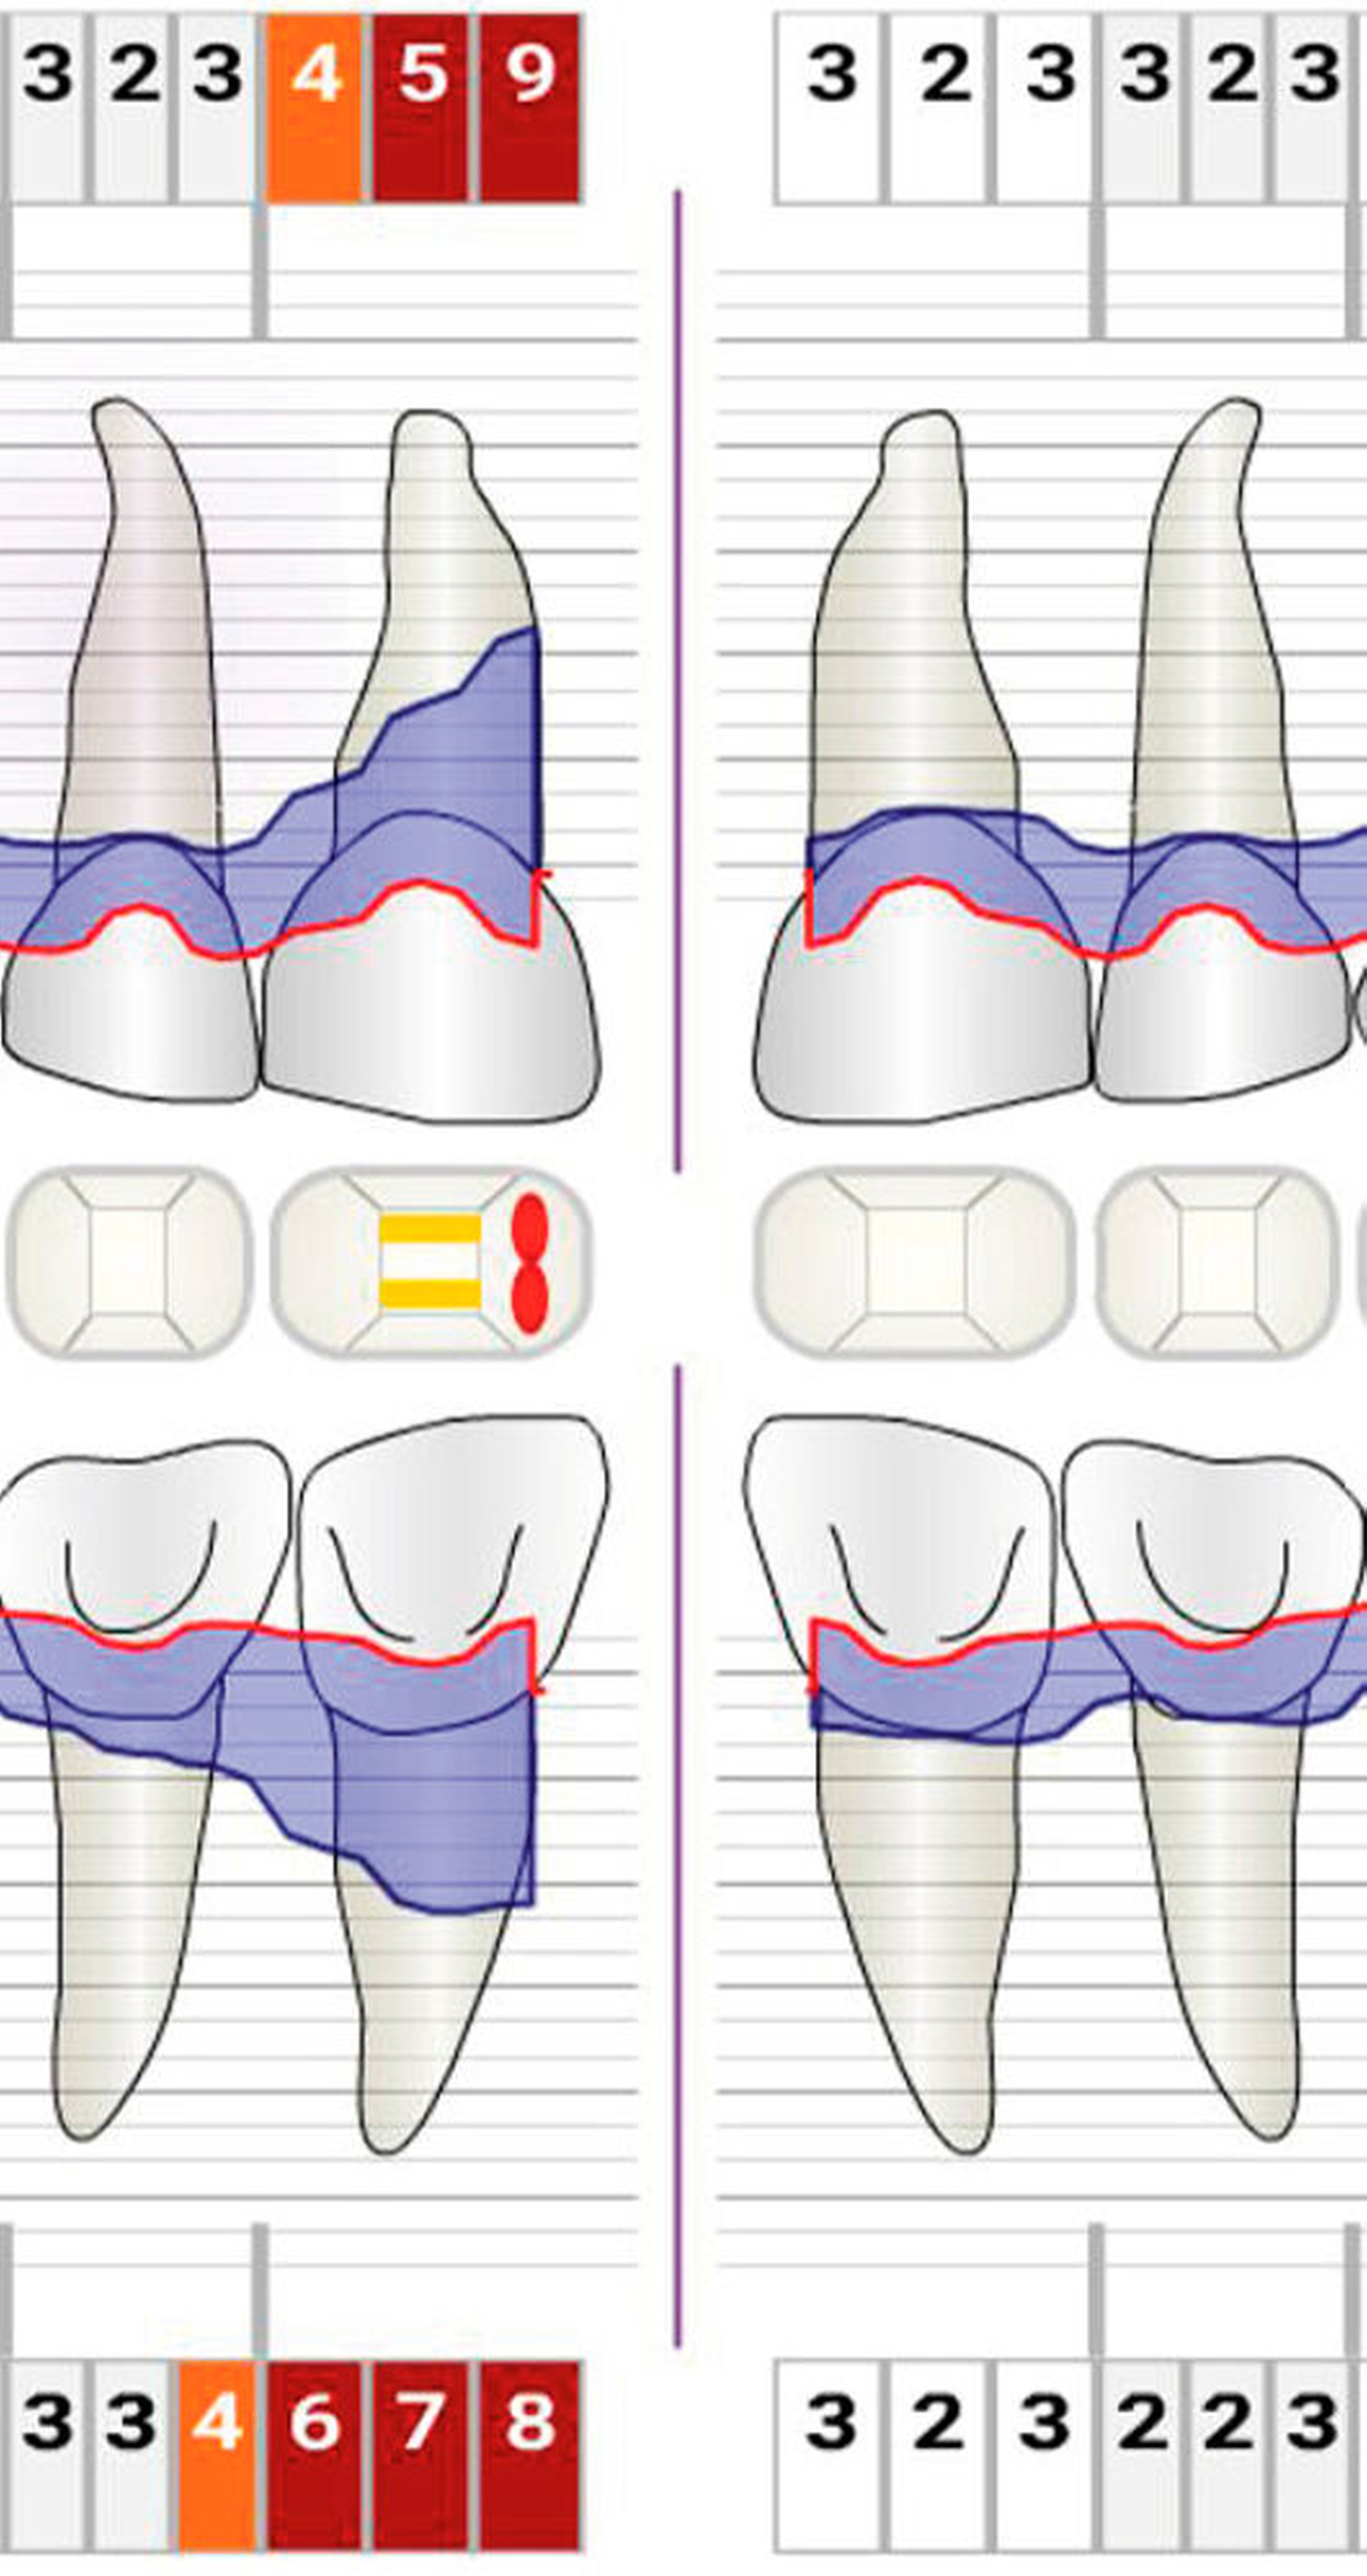

Die Anwendung mikrochirurgischer Prinzipien wurde im Zusammenhang mit unterschiedlichen parodontal-chirurgischen Eingriffen wissenschaftlich untersucht. Cortellini et al. behandelten 26 Patienten mit tiefen intra-ossären Defekten mittels geführter Geweberegeneration unter Anwendung eines Operationsmikroskops. Die Ergebnisse zeigten eine Zunahme des klinischen Attachmentlevels von im Mittel 82,8 ± 14,7 Prozent. Die Reduktion der Sondierungstiefen um 5,8 ± 1,4 mm ging mit einer minimalen Rezessionsbildung von 0,4 ± 0,7 mm einher. Die Autoren sahen die Vergrößerung des Operationsfelds und die bessere Beleuchtung als maßgeblich an, um die Gewebe präzise und atraumatisch zu behandeln. In 92,3 Prozent der Fälle kam es zu einer primären Wundheilung, die über den gesamten Wundheilungsprozess bestehen blieb [Cortellini & Tonetti, 2001].

In einer weiteren Studie der gleichen Gruppe wurden isolierte intraossäre Knochendefekte bei 13 Patienten mit einer minimalinvasiven chirurgischen Technik (MIST) und der Applikation von Schmelz-Matrix-Proteinen behandelt. Ein Operationsmikroskop sowie mikrochirurgische Instrumente und Nahtmaterialien wurden verwendet. Es kam zu keinen Ödemen oder Hämatomen. Die Patienten gaben keine Schmerzen an. Der klinische Attachmentlevel war nach einem Jahr um 88,7 ± 20,7 Prozent höher als zu Beginn der Behandlung. Eine primäre Wundheilung konnte in 92,3 Prozent erreicht werden [Cortellini & Tonetti, 2007]. Auch bei der Behandlung nebeneinanderliegender intraossärer Knochendefekte kam es unter den gleichen Bedingungen zu einer Zunahme des klinischen Attachmentlevels um 83 ± 20 Prozent. Die Patienten gaben moderate Schmerzen für den Zeitraum der ersten 21 ± 5 Stunden an. Eine primäre Wundheilung konnte in 100 Prozent der Fälle erreicht werden [Cortellini et al., 2008].

Cairo et al. untersuchten die Behandlung parodontaler Taschen mit flachen oder moderaten Knochendefekten (kleiner/gleich 3 mm) in der ästhetischen Zone unter Anwendung der „Fibre Retention“-Technik in Kombination mit Papillenerhaltungslappen. Die Heilung verlief in 100 Prozent der Fälle per primam und ohne besondere Vorkommnisse. Die Verwendung des Operationsmikroskops verbesserte die visuelle Wahrnehmung und erhellte das Operationsfeld, so dass die in der Tiefe der Defekte verbliebenen parodontalen Fasern besser identifiziert und erhalten werden konnten. Das Ergebnis zeigte eine Zunahme des klinischen Attachmentlevels, eine Reduktion der Sondierungstiefen und geringe Rezessionsausbildungen. Es gab keine postoperativen Komplikationen und die Patienten waren mit dem ästhetischen Ergebnis zufrieden [Cairo et al., 2008].